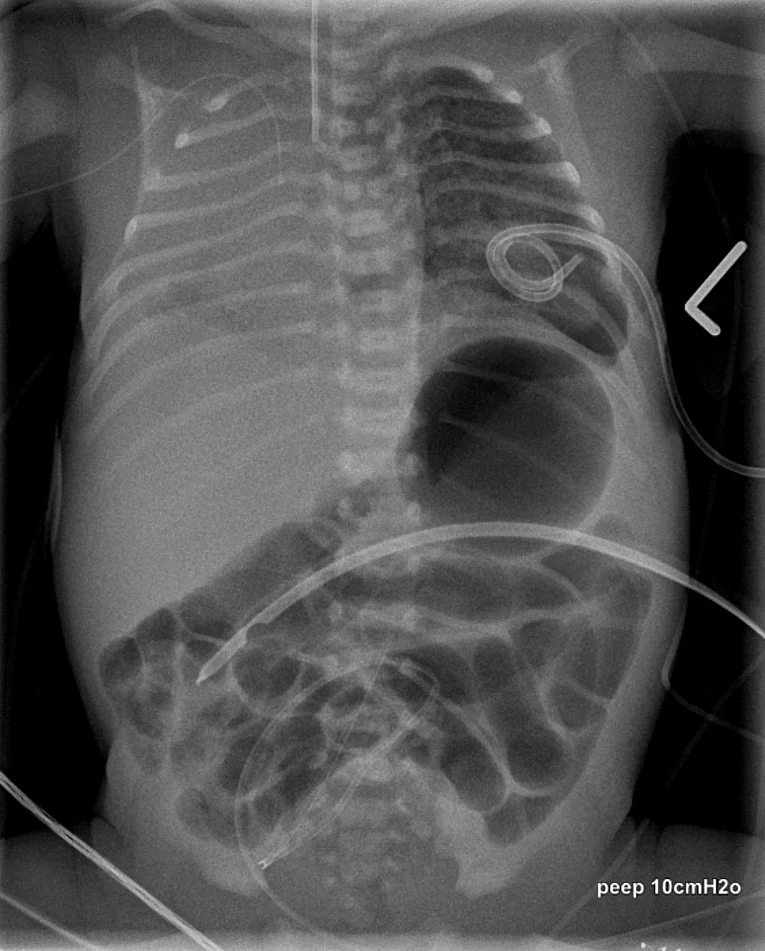

Das kongenitale lobäre Emphysem ist gekennzeichnet durch eine Überblähung eines Lungenlappens, die durch Kompensation eines zu kleinen (hypoplastischen) Lungenlappens auf der Gegenseite entsteht.